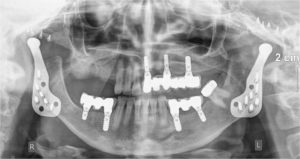

Χειρουργική Κροταφογναθικής Διάρθρωσης